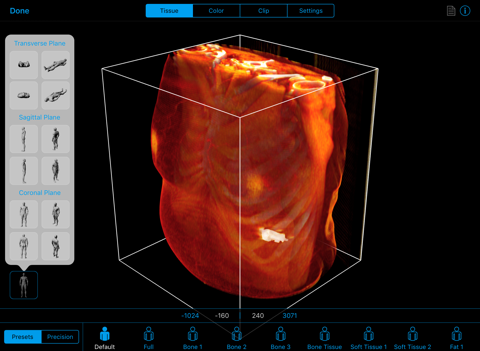

The BodyViz iPad app is a key component of the world’s most scalable 3D MRI/CT visualization suite for anatomy education and medical simulation. The BodyViz iPad app allows users to interactively rotate, pan and zoom through a patients virtual anatomy in 3D, using the familiar and intuitive iOS gesture interface. Clipping planes can be created and moved for virtual dissection to expose internal structures of the patient. Users can choose the tissue density they wish to view, such as harder tissues (e.g., bone, muscle) or softer tissue, like fat or skin. They can also choose from a variety of colors to enhance organs and other features of the data. Finally, the BodyViz iPad app enables users to view spatially registered annotations created with the BodyViz desktop application that can allow labeling of anatomical data as well as providing descriptions, web links, and images.

- Volume rendering mode offers interactive 3D representations.

- Zoom, pan, and rotate 3D representations with familiar iOS interaction gestures

- Tissue mode that allows different densities to be viewed in real-time from preset or user defined values

- Multiple coloring schemes available in 2D and 3D modes